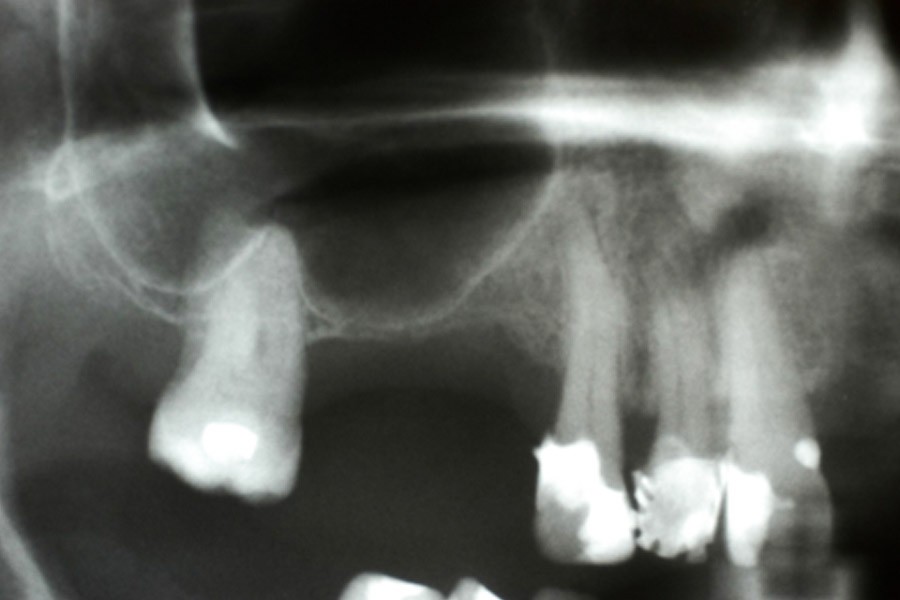

Przed podjęciem leczenia należy określić stopień zaniku kości szczęk oraz żuchwy. W tym celu przeprowadza się badanie kliniczne oraz odpowiednią diagnostykę obrazową pacjenta. Uwzględnia ona zdjęcie panoramiczne OPG jako podstawę dwuwymiarowego obrazowania podłoża kostnego oraz możliwe jest badanie tomograficzne CT lub bardziej precyzyjna tomografia stożkowa CBCT. Opcjonalnie wykorzystywana diagnostycznie tomografia pozwala na bardziej wnikliwą ocenę stopnia zaniku kości w trójwymiarowym, przestrzennym obrazie.

Zabiegiem, który rozwiązuje ten problem, jest podniesienie dna zatoki szczękowej, czyli odbudowa kostna w okolicy zębów trzonowych. Ubytek kości uzupełniany jest materiałem kościotwórczym, który układany jest pod błoną wyścielającą zatokę szczękową, zwaną membraną Schneidera. Zmniejszając objętość zatoki szczękowej, tworzy się tym samym stabilną strukturę kostną, umożliwiającą zabieg implantacji wszczepów śródkostnych.

Zatoki szczękowe to symetrycznie umieszczone w kościach szczęk przestrzenie powietrzne, posiadające komunikację z jamą nosa. Średnio pojemność zatok wynosi 24 cm3, a ściany wyścielone są błoną śluzową (membrana Schneidera). Dno zatoki szczękowej stanowi wyrostek zębodołowy, w którym umieszczone są zęby, często zlokalizowane tuż pod cienką wyściółką zatoki. Statystycznie najwęższy obszar kostny w tej strefie zlokalizowany jest na wysokości zębodołów pierwszego i drugiego zęba trzonowego.